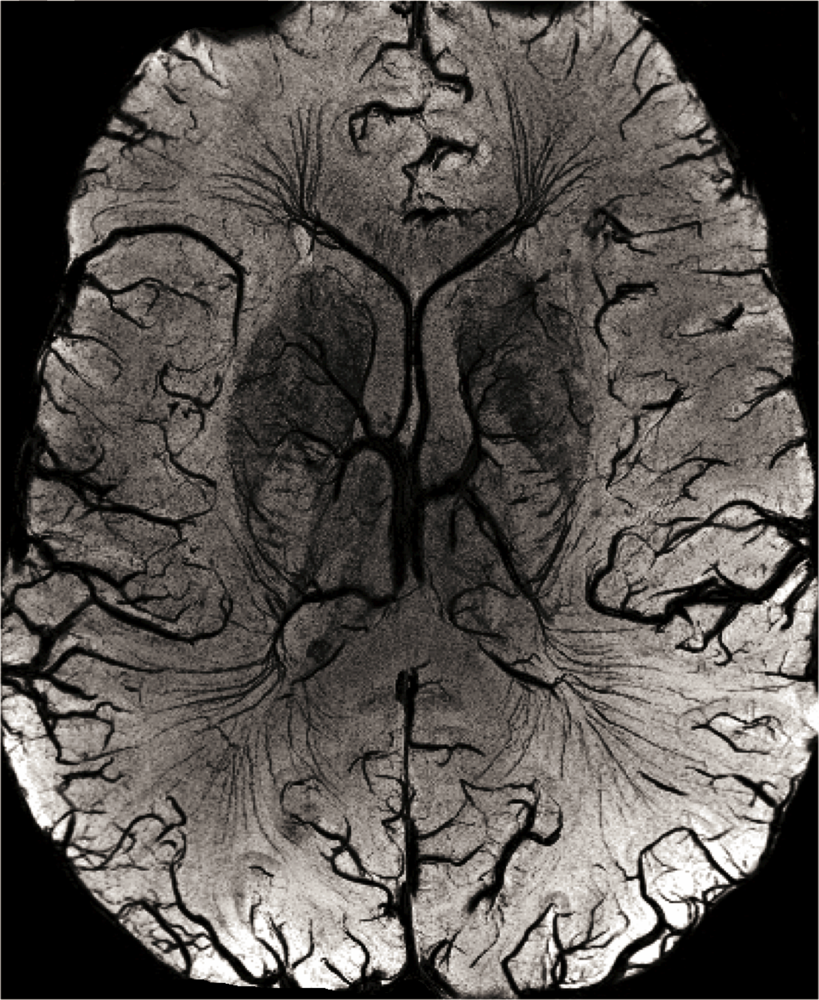

2.1. High-Resolution Structural MRI

Structural brain imaging: